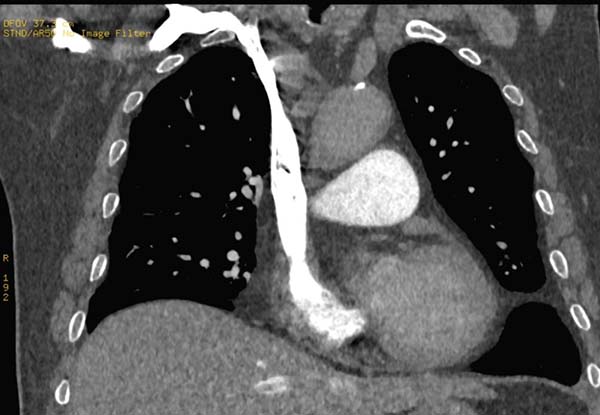

当对比剂到达锁骨下静脉、头臂静脉时,左右两侧的路径发生分歧,右锁骨下静脉→右头臂静脉路径距右心房的距离要明显短于左锁骨下静脉→左头臂静脉路径,右锁骨下静脉连接右头臂静脉后直接汇入右心房,而左锁骨下静脉连接左头臂静脉的同时需跨越左颈总动脉、头臂干,部分情况下还会受到主动脉弓的影响。

如下图所示

2、常规优先选择右上肢留置穿刺针的原因

增强CT在高速团注时应优先选择血管条件好、管径粗、伪影少、路途短的血管快速注射对比剂完成循环。大多数人右上肢血管管径粗、走行直,没有太多的弯曲,对比剂经头臂静脉直接进入上腔静脉的路程短且通畅。

右锁骨下静脉经头臂静脉直接进入上腔静脉